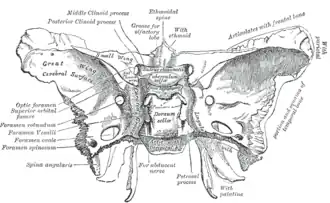

Forames e fissuras[4]

- Canal óptico - nervo óptico e artéria oftálmica

- Forame redondo - nervo maxilar (V²)

- Forame oval - nervo mandibular (V3), artéria meníngea acessória

- Forame espinhoso - artéria meníngea média

- Canal pterigoide

Juntamente com o osso frontal:

- Fissura orbitária superior - Nervos oculomotor (III), troclear (IV) abducente (VI) e ramo oftálmico do trigêmeo (V¹),artéria oftálmica e veia oftálmica

- Fissura orbitária inferior - nervo maxilar (segunda divisão do nervo trigêmeo), artéria infraorbital e veio infraorbital

Visto por baixo

Visto de cima